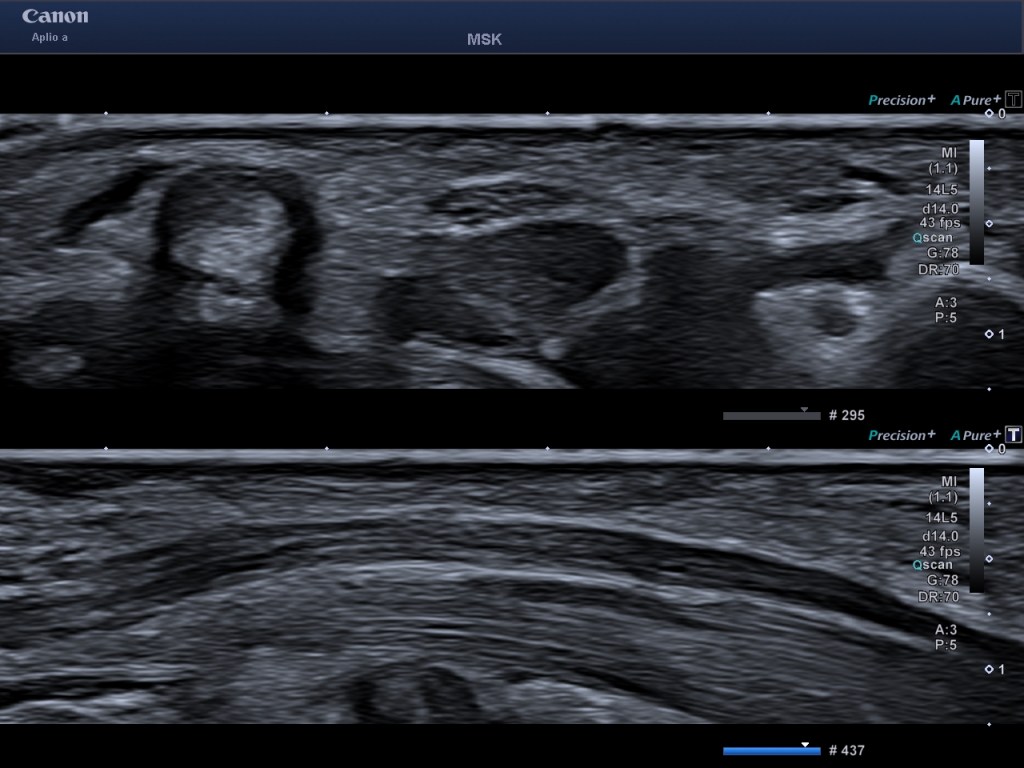

- Índice Mecánico (IM): El Índice Mecánico es un parámetro que se utiliza para medir el riesgo potencial de efectos mecánicos no térmicos (como la cavitación) producidos por el ultrasonido en los tejidos. Un valor más alto de IM indica un mayor riesgo.

- Límites de Seguridad: Por razones de seguridad, existen límites recomendados para la potencia de transmisión ecográfica y el IM (Índice Mecánico), ODS siempre visible en pantalla. Estos límites son diferentes para distintas aplicaciones:

- General: Un límite común es 1.9, utilizado para la mayoría de las estructuras, incluyendo aplicaciones fetales, vasculares y cardíacas. Este límite busca equilibrar la calidad de la imagen con la seguridad del paciente. Siempre es obligado el uso del criterio ALARA.